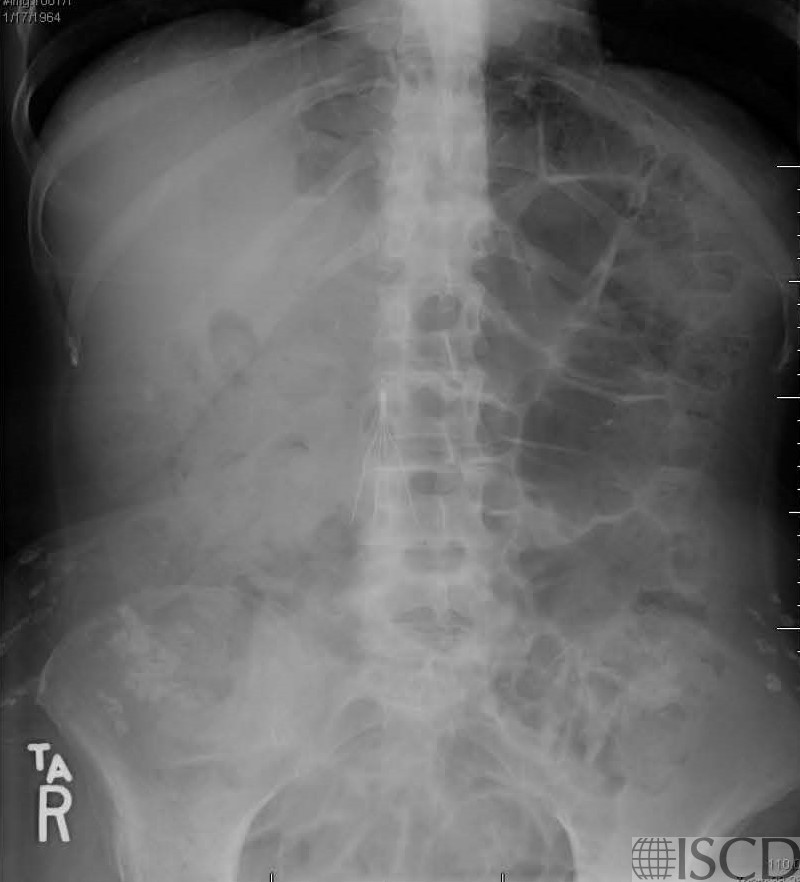

The corresponding abdominal x-ray shows the IVC filter.

There is an IVC filter overlying L2 and L3.